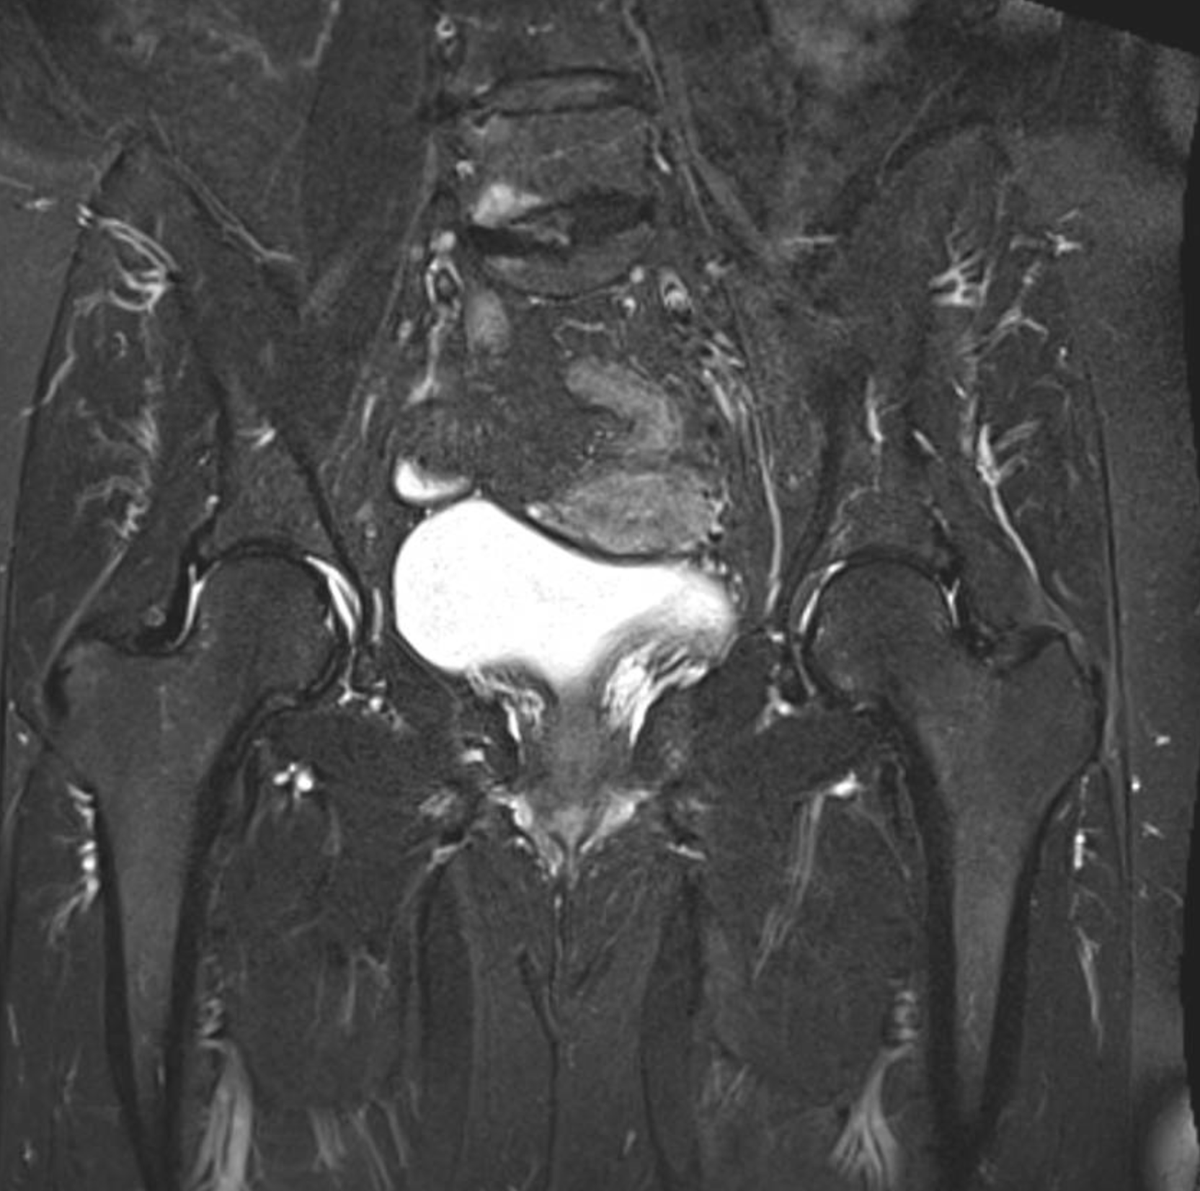

Consent ✅

F 60s

Years of diffuse R gluteal, hip & thigh pain, constant, stairs & sitting aggravates

Seen by orthopaedics to evaluate hip & knee (previous patellectomy this side) - referred to me as unable to identify pain driver & MRI scans 'normal'

MRI pelvis - hip joints & lateral soft tissues are fine

Clear suspect for her pain though, even on first glance - what do you see?

I've put the skyline view x-ray of her knee in too coz it's cool

Always check the images yourself - and bear in mind can pick up helpful pathology on non-dedicated series so worth scrutinising it all